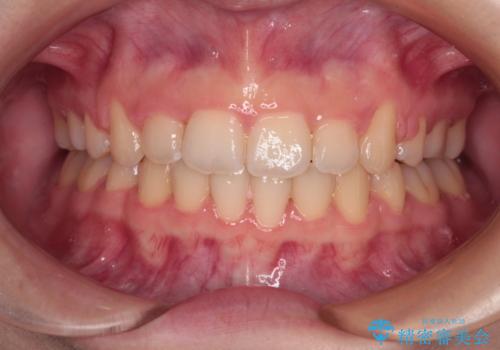

上下の八重歯とクロスバイト ワイヤー装置での抜歯矯正

- 八重歯とクロスバイトを気にして来院された患者様です。

上下ともに八重歯が顕著であり、前歯のクロスバイトがあったため、上下左右の第一小臼歯4本を抜歯し、ワイヤー装置での抜歯矯正を行うこととしました。